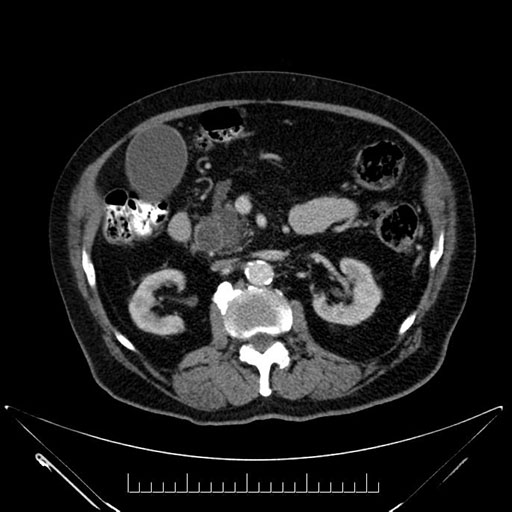

Axial - stented

Imaging analysis